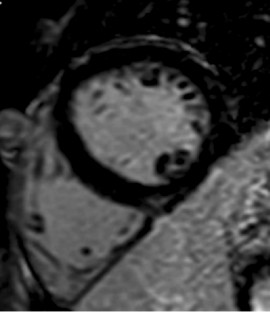

Fig. 2